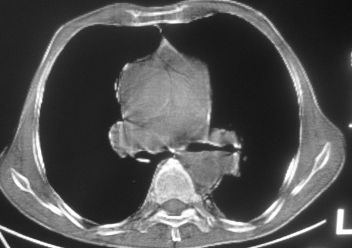

以下是引用南沙在2007-10-7 10:44:00的发言:[br]左下肺不张.[br]肺癌可能性大?

以下是引用卜一在2007-10-7 9:38:00的发言:[br]左下肺胸膜下团片影,内见含气支气管像,临近胸膜未见增厚。多考虑:1 左下肺炎症,建议消炎后复查!2 不除外肺隔离症合并感染!